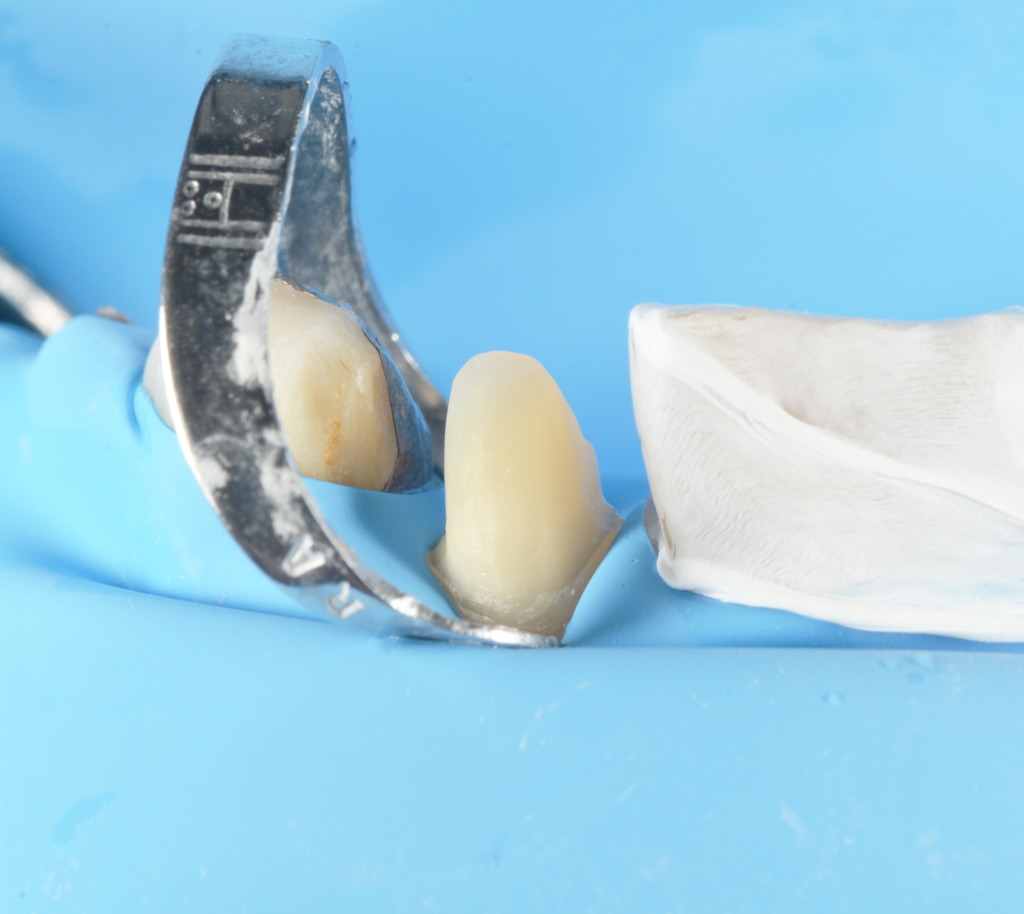

using Hawe steel matrix bands as scaffold, a build up is performed with flowable and packable composite. To increase the stabilization of the latter is used liquid rubberdam.

Isolated fractured tooth

fracture and martix scaffold

morphologic build up